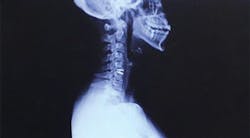

A herniated disk was the cause of years of pain resulting from improper workplace ergonomics

While it did take some time, a neurologist finally confirmed that a herniated disk in my neck was the cause of my pain. I was initially prescribed one month of physical therapy, which eventually turned into three. The co-pays and the unpaid sick time I needed to take away from the office added up to approximately $5,000. Unfortunately, physical therapy was only a short-term fix, and the herniated disk continued to wreak havoc on my life.

Seeing the scar on my neck, resulting from the subsequent cervical disk replacement surgery, patients were more willing to lie back farther and turn toward me when I asked. I frequently ask myself if surgery could have been avoided if I had advocated for myself and required my patients to accommodate me. If I had invested in my loupes and my saddle stool earlier, could that have helped?